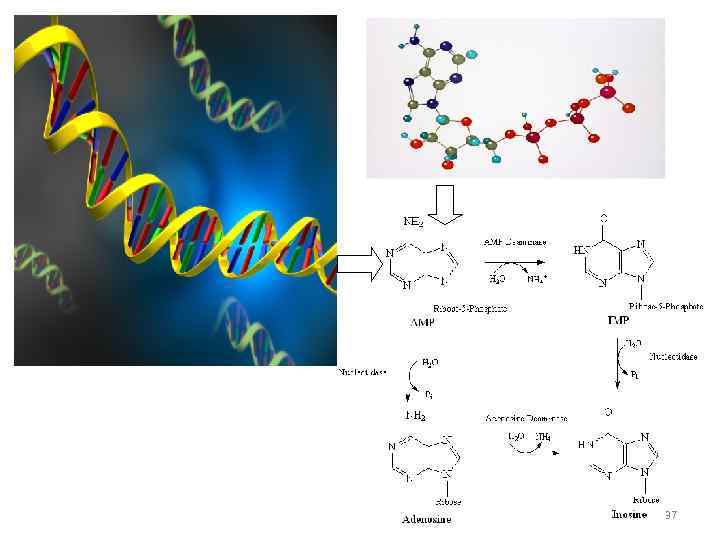

37